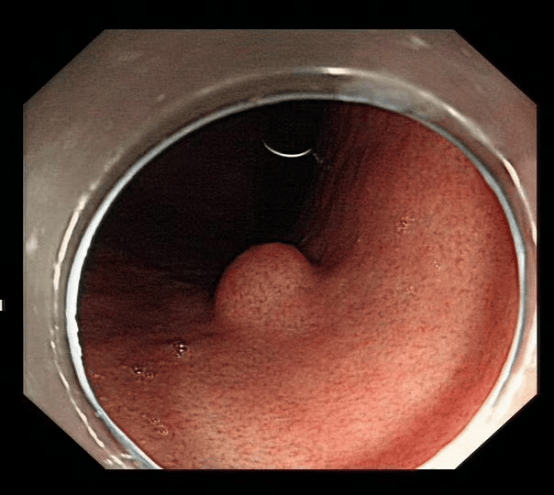

患者在胃镜检查时发现胃粘膜下肿物,考虑间质瘤可能,如不及时切除有可能恶变,需行内镜下粘膜剥离术(ESD)。由于此手术创伤小、恢复快,经与患者及家属沟通后,完善相关术前准备后,在安徽省第二人民医院消化内科王俊先主任指导下,消化内科、内镜中心及麻醉科医护人员的密切配合下,成功为患者进行手术,术中无明显出血、穿孔,术后各项生理指标正常,手术取得圆满成功。

ESD即内镜粘膜下剥离术,方法是在内镜粘膜下注射基础上利用几种特殊的高频电刀,将病变所在粘膜剥离。通过ESD可完整的切除病变,达到根治消化道肿瘤的效果。